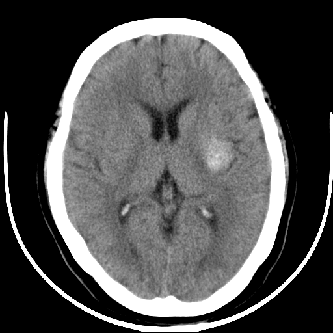

标题: CT4588:是出血吗?

44 f,平时头晕,有高血压病史,近日加重。其它检查无异常。

图象ct值是多少?品眼看密度像出血但周围没有水肿带也没有占位效应很难说

有肢体活动障碍吗?离左侧内囊后肢很近。不像是出血,如果是出血吸收期,周围应该有水肿

尽管密度类似于出血,但其密度明显不均匀,中间有多枚小点状致密影似钙化。同时,病灶周围没有水肿,没有占位效应,临床又没有其他症状。

首先考虑动静脉畸形,建议增强。

左侧豆状核后部不均匀高密度影,中间有斑点状钙化灶,周围无水肿及占位效应,考虑血管瘤。